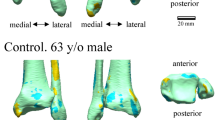

The deviation color maps of the control group indicated that the tali were essentially bilaterally symmetrical in the control group (Fig. 1). On the other hand, the deviation color map of stage 3a showed some osteophyte formation along the anteromedial margin of the trochlea articular surface. (Fig. 2) In stage 3b OA tali, osteophyte formation around the lateral process was also observed. (Fig. 3) In stage 4 OA tali, bone resorption on the anteromedial trochlear articular surface was observed (Fig. 4), indicating that the trochlear articular surface of OA tali inclined medially on the coronal plane. However, deformation of posterior calcaneal articular surfaces was found to be relatively minor, regardless of the severity of ankle OA (Figs. 2–4).

Plain radiographs and deviation color maps of the osteoarthritis (OA) groups in stage 3a. Deviation color maps of three representative examples are presented. The red and blue colors are deviations of the OA talus outside and inside of the healthy talus. See Fig. 1 and text for more details.

Plain radiographs and deviation color maps of the OA groups in stage 3b. Deviation color maps of three representative examples are presented. The red and blue colors are deviations of the OA talus outside and inside of the healthy talus. See Fig. 1 and text for more details.

Plain radiographs and deviation color maps of the OA groups in stage 4. Deviation color maps of three representative examples are presented. The red and blue colors are deviations of the OA talus outside and inside of the healthy talus. See Fig. 1 and text for more details.